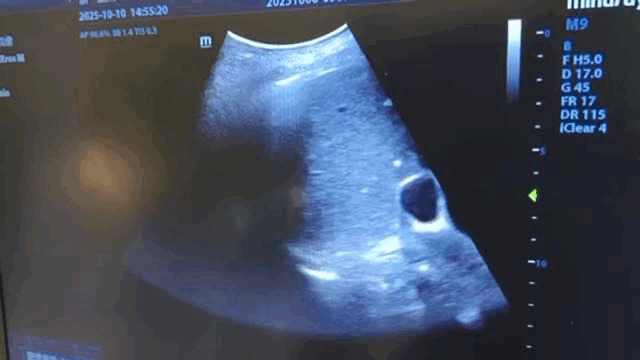

右下肺透亮度增加,是否有气胸?查体右下肺呼吸音基本和左侧一致,超声有胸膜滑动征;

因此继续观察并早上复查胸片。